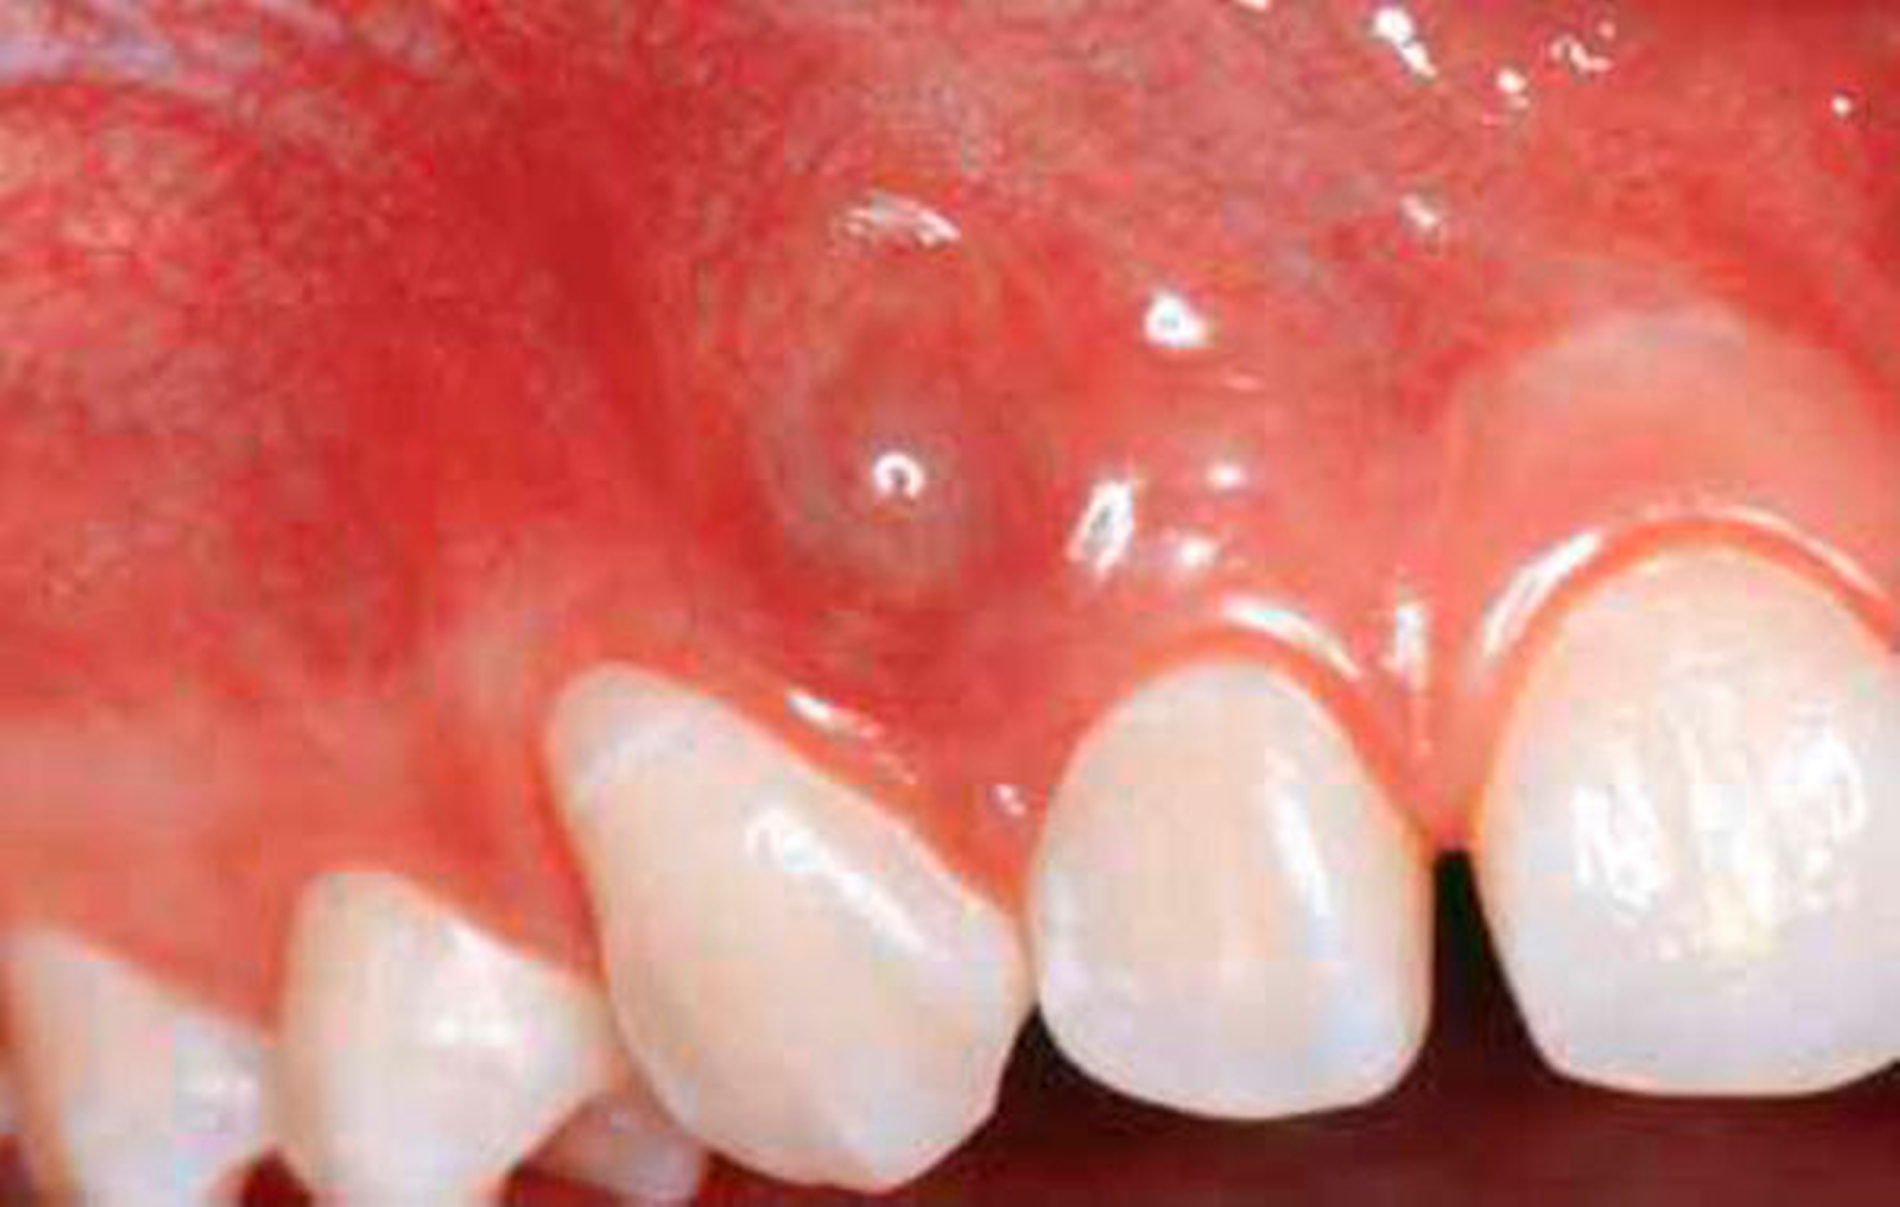

Die GZ wurde auch der parodontalen Zyste gegenübergestellt. Während letztere zwischen den Wurzeln sämtlicher Zähne entstehen kann, erscheint die GZ typischerweise nur zwischen dem lateralen Schneidezahn und dem Eckzahn, dort wo sich Prämaxilla und Maxilla vereinen. Es wurde Wert darauf gelegt, dass die Zyste zwischen parodontal und pulpal gesunden Zähnen vorkommt und somit ein Zweifel an ihrem fissuralen Ursprung ausgeschlossen ist. Die GZ verdrängt die Wurzeln des lateralen Incisivus und des Eckzahns, was als erstes klinisches Zeichen beschrieben wird. Später kann es zu einer Vorwölbung der vestibulären Schleimhaut kommen, oft assoziiert mit einem Druckgefühl (Abb. 1 bis 5).

Diese übereinstimmenden Befunde lassen vermuten, dass die Entzündung ein wichtiger Faktor in der Entwicklung der IPC spielt. Die Autoren [Vedtofte & Holmstrup, 1989] vermuten, dass die IPC durch eine Perikoronitis während der Zahneruption initiiert wird, wie dies bereits 1976 postuliert wurde [Craig, 1976]. Malassez’sche Epithelreste oder reduziertes Schmelzepithel wurden als wahrscheinlichster Ursprung des Zystenepithels angesehen. Die Beobachtung, dass solche Zysten spätestens wenige Jahre nach dem Eckzahndurchbruch im Oberkiefer auftreten, lässt vermuten, dass ein Zusammenhang mit dem Zahndurchbruch besteht [Vedtofte & Holmstrup, 1989]. Ein ähnlicher Zusammenhang wurde bereits bei den IPC im Unterkiefer beschrieben. Die Autoren stellen abschließend fest, dass bisher in der Literatur als GZ bezeichnete Zysten in Wirklichkeit Manifestationen einer IPC sind [Vedtofte & Praetorius, 1989].